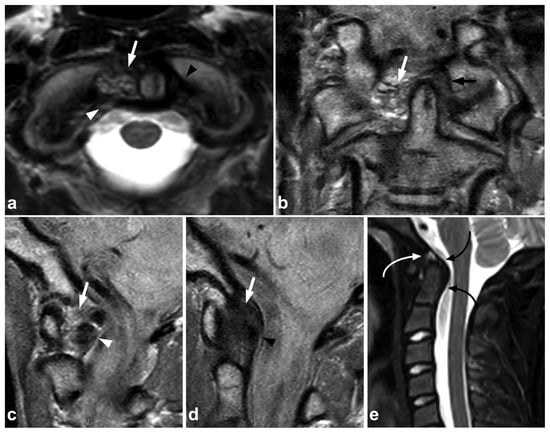

7.4. Imaging Appearances of Normal Skeletal Maturation

Every radiologist performing pediatric imaging must be aware of the fundamentals of skeletal maturation [87]. On the MR imaging of acute pediatric trauma, one of the potential pitfalls is the physiological high T2 signal at the physis and metaphyseal spongiosa of the secondary ossification centers [88]. This can be misinterpreted as traumatic edema if the normal anatomy and development of the ossification centers are not kept in mind (Figure 20). On the other hand, an unfused vertebral ring apophysis [89,90], apophyseal injuries [91], and other calcifications not related to the acute injury are readily distinguished from fractures with the absence of edema (Figure 21).

Figure 20.

(a) Axial fat-suppressed T2-weighted. (b) Coronal STIR. An 11-year-old male, lower back/pelvic pain after falling on ice. MRI demonstrates symmetric zones of bright T2 signal (arrows) at the secondary ossification centers of the sacrum and iliac bone, characteristic of normal skeletal maturation. With the symptoms and injury mechanism in such a case, the findings could be misinterpreted as traumatic edema if the normal skeletal maturation and anatomy of the ossification centers are not kept in mind.